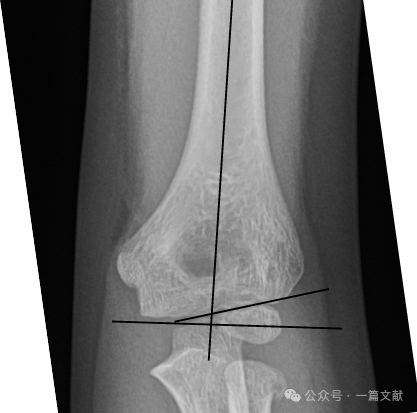

Alignment on AP Radiograph:

* Baumann’s Angle: Formed by a line perpendicular to the humeral axis and a line through the capitellar physis. This angle has a wide normal range (9-26 degrees). The best method to determine normality is to obtain a contralateral comparison view.